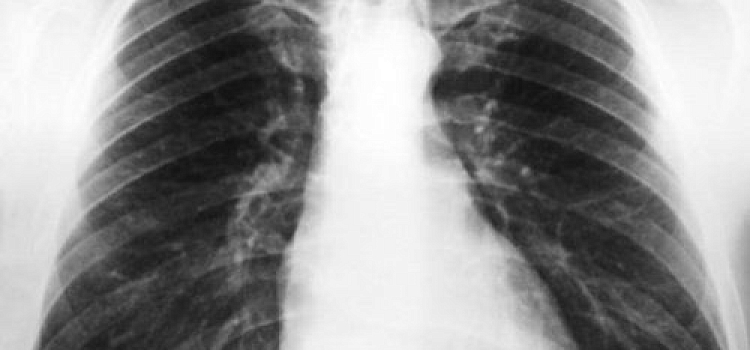

В преддверии Всемирного дня борьбы с туберкулезом, 18 марта, с 10:00 до 14:00 на базе флюорографической станции (Ярославль, ул. Собинова, 24) будет проходить день открытых дверей. В рамках акции «Проверь себя» все желающие могут пройти ФЛГ-обследование и получить консультацию ведущих врачей-фтизиатров.

Туберкулез — это заразное инфекционное заболевание, пострадать от которого может каждый. В начальной стадии его можно легко излечить, однако обычно человек в этот период считает себя здоровым. Выявить туберкулез у взрослых можно только по флюорографии.